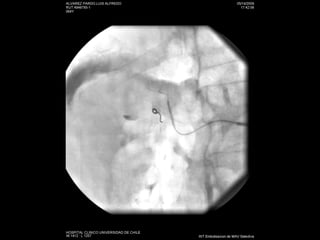

Nefrostomías  Éxito cercano a un 100% Complicaciones 4% hemorragia-infección Inserción anterógrada de catéter doble J

Nefrostomías Éxitocercano a un 100% Complicaciones 4% hemorragia-infección Inserción anterógrada de catéter doble J